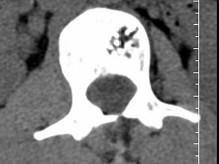

问题 根据所提供的图像,选择最可能的诊断 ( )

选项 A、退行性变 B、骨质疏松 C、多发性骨转移 D、骨血管瘤 E、骨结核

答案 D